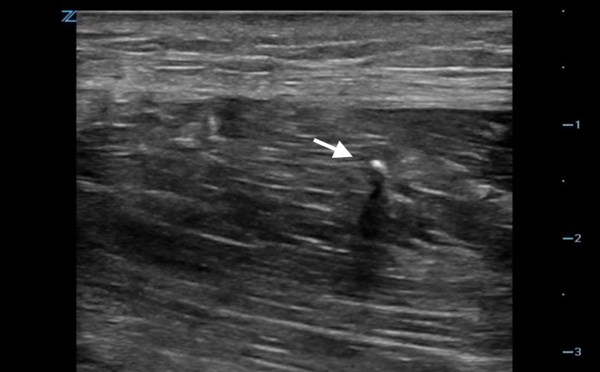

Visualizing the Needle

During the block, keeping the tip in view is of critical importance. Doing so will result in the highest quality block and avoid the most devastating complications.

- If the tip is not clear, inject 0.5 cc of local anesthetic. This will deform the tissue surrounding the tip, and the anechoic fluid bolus should highlight the tip.